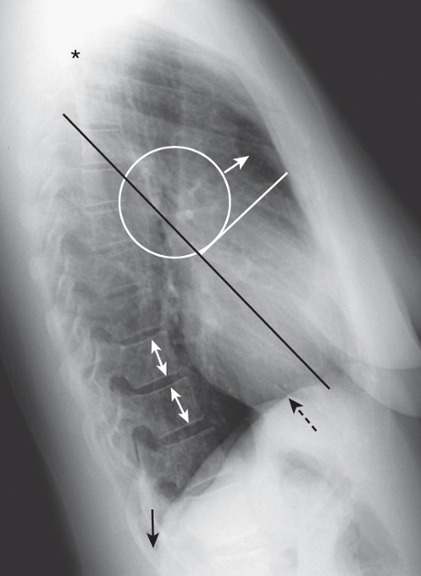

Penetration

The degree of penetration is adequate since we can see the spine (solid white arrows) through the heart.

Underpenetration

Underpenetration – cannot see thoracic spine through the heart